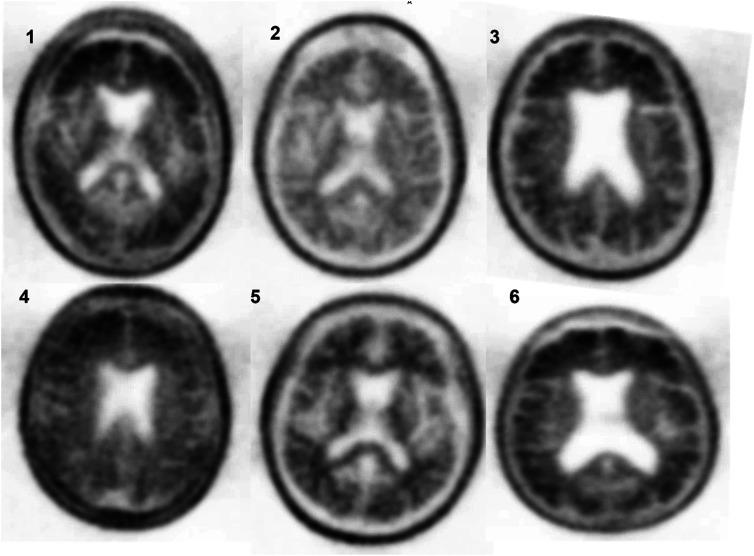

In older adults with cognitive decline and epilepsy, diagnosing the etiology of cognitive decline is challenging. We identified 6 subjects enrolled in the Imaging Dementia-Evidence of Amyloid Imaging Scanning (IDEAS) study and nonlesional epilepsy. Three cognitive neurologists reviewed each case to determine the likelihood of underlying Alzheimer's disease (AD) pathology. Their impressions were compared to amyloid PET findings. In 3 cases the impression was concordant with PET findings. In 2 cases "possibly suggestive," the PET reduced diagnostic uncertainty, with 1 having a PET without elevated amyloid and the other PET with intermediate amyloid. In the remaining case with lack of reviewer concordance, the significance of PET with elevated amyloid remains uncertain. This case series highlights that in individuals with a history of epilepsy and cognitive decline, amyloid PET can be a useful tool in evaluating the etiology of cognitive decline when used in an appropriate context.

Abstract Image